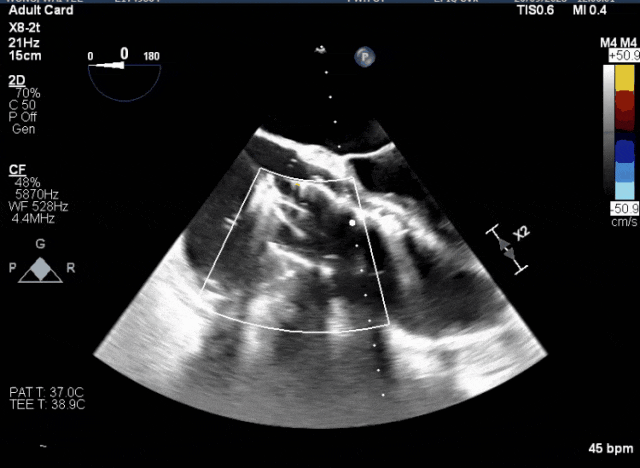

術中TEE成像困難,偽影干擾

術后DSA、超聲顯示人工瓣膜穩定性良好,瓣葉啟閉正常,無瓣周漏

術中TEE觀察夾持件的位置